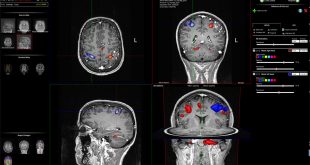

نوروسافاری| طبق مطالعه جدید محققان، افراد دارای سطح تحصیلات بالاتر بسیار در معرض ابتلا به انواع تومورهای مغزی قرار دارند. مطالعه محققان سوئدی نشان می دهد افراد دارای تحصیلات دانشگاهی، مشاغل تخصصی یا حقوق بالا بیش از افراد دارای تحصیلات پایین تر، مبتلا به تومور مغزی می شوند. …